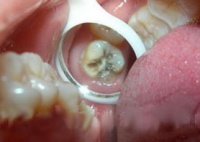

龋齿最容易发生在磨牙双尖牙的咬面小窝、裂沟中,以及相邻牙齿的接触面。前者称为窝沟龋,后者称为邻面龋。儿童发生在牙颈部的龋齿极少,只在严重营养不良或某些全身性疾病使体质极度虚弱时才可见到。根据龋齿破坏的程度,临床可分为浅龋、中龋和深龋。

• 浅龋 龋蚀破坏只在釉质内,初期表现为釉质出现褐色或黑褐色斑点或斑块,表面粗糙。继而形成表面破坏。邻面龋开始发生在接触面下方,窝沟龋则多开始在沟内,早期都不容易看到。只有发生在窝沟口时才可以看到,但儿童牙齿窝沟口处又容易有食物的色素沉着,医师检查不仔细也会误诊或漏诊。浅龋没有自觉症状

• 中龋:龋蚀已达到牙本质,形成牙本质浅层龋洞。病儿对冷水、冷气或甜、酸食物会感到牙齿酸痛,但刺激去掉以后,症状立即消失。这是在为牙本质对刺激感觉过敏的缘故。中龋及时得到治疗效果良好。

• 深龋:龋蚀已达到牙本质深层,接近牙髓,或已影响牙髓。患儿对冷、热、酸、甜都有痛感,特别对热敏感,一败涂地去掉以后,疼痛仍持续一定时间才逐渐消失。这时多数需要作牙髓治疗以保存牙齿。